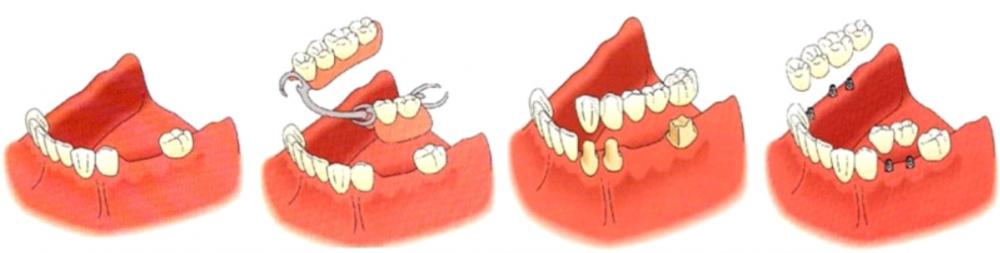

Existen varios tipos de prótesis dentales, cada una diseñada para cumplir diferentes necesidades y circunstancias. A continuación, mencionamos algunos tipos de prótesis dentales más comunes :

Prótesis dentales completas removibles: También conocidas como dentaduras postizas, son utilizadas cuando se han perdido todos los dientes de la mandíbula superior, inferior o ambas. Son removibles y se apoyan en la encía y el hueso subyacente.

Prótesis dentales parciales removibles: Estas prótesis se utilizan cuando hay algunos dientes naturales aún presentes en la boca. Se sujetan mediante ganchos o dispositivos de anclaje a los dientes adyacentes, y son removibles.

Prótesis dentales fijas: También conocidas como puentes dentales, son prótesis que se cementan o se adhieren de manera permanente a los dientes naturales o a los implantes dentales. Están diseñadas para reemplazar uno o varios dientes perdidos y restaurar la función y la apariencia natural.

Prótesis dentales implantosoportadas: Estas prótesis se fijan sobre implantes dentales que están integrados en el hueso. Proporcionan una mayor estabilidad y función, y pueden ser utilizadas para reemplazar uno o varios dientes perdidos.